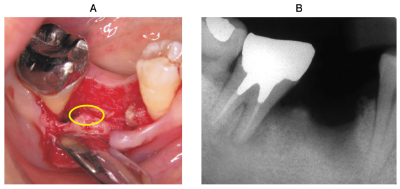

49歳の女性。慢性歯周炎と診断し、歯周基本治療を行い、下顎右側第一大臼歯は予後不良と判断し抜去した。再評価の結果、下顎右側第二大臼歯に歯周外科治療を行うこととした。術中の口腔内写真、エックス線写真及び器具の写真を別に示す。再評価時の歯周組織検査結果の一部を表に示す。

丸印で示す部分の処置に使用する器具はどれか。2つ選べ。